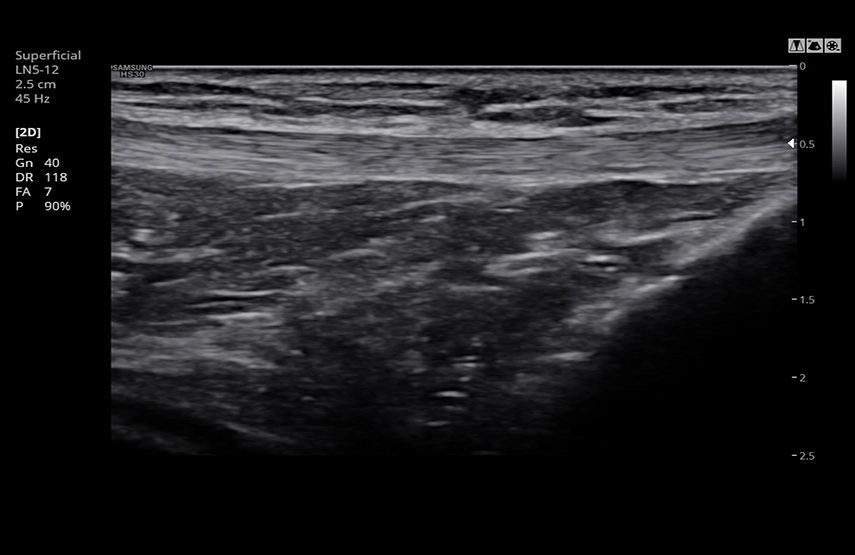

Многофункциональный ультразвуковой сканер с оптимальным набором функций и режимов сканирования для всех видов исследований, включая цветной, энергетический, направленный энергетический, тканевой, импульсный и непрерывноволновой допплер.

УЗИ сканер Samsung Medison HS30 – удобный аппарат, приспособленный под нужды врачей. В строении сканера предусмотрены держатели для кабелей датчиков, нагреватель геля, боковой карман, чтобы необходимые вещи всегда были под рукой. Помимо стандартных режимов сканирования поддерживает современные функции, позволяющие расширить возможности диагностики и повысить ее точность, Elastoscan, Strain+, NeedleMate и др. Система имеет оптимальное соотношение цена/качество/функционал в своем сегменте и станет прекрасным выбором для частного кабинета или небольшой клиники общего профиля. Абдоминальные исследования, акушерство, гинекология, кардиология, ангиология, нефрология, урология, онкология, педиатрия, неонатология, исследования костно-мышечной системы, поверхностных органов, молочной железы, ТКД.

- Линейный датчик LN5-12, 5-12 МГц, апертура 38 мм;

Колено в ClearVision